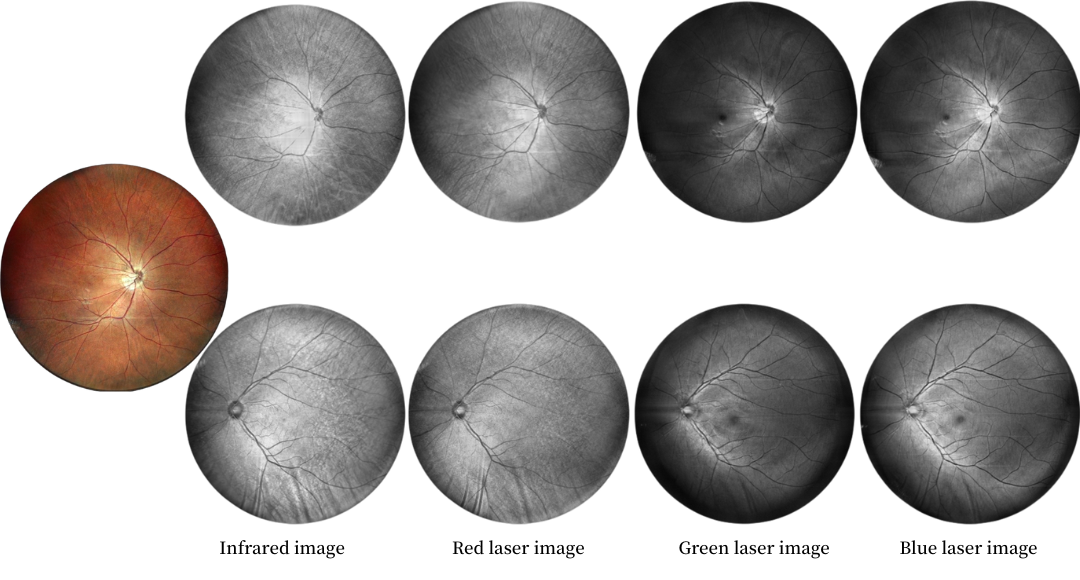

Multi-wavelengh Laser Imaging

Single Infrared Laser

Infrared laser wavelength 840 for retina imaging at 130 degrees

Double Lasers

Infrared laser 840 wavelength and 520 green laser for retina and choroid imaging at 130 degrees

Four Lasers

Infrared laser and green+red+blue laser for retina and choroid imaging at 130 degrees